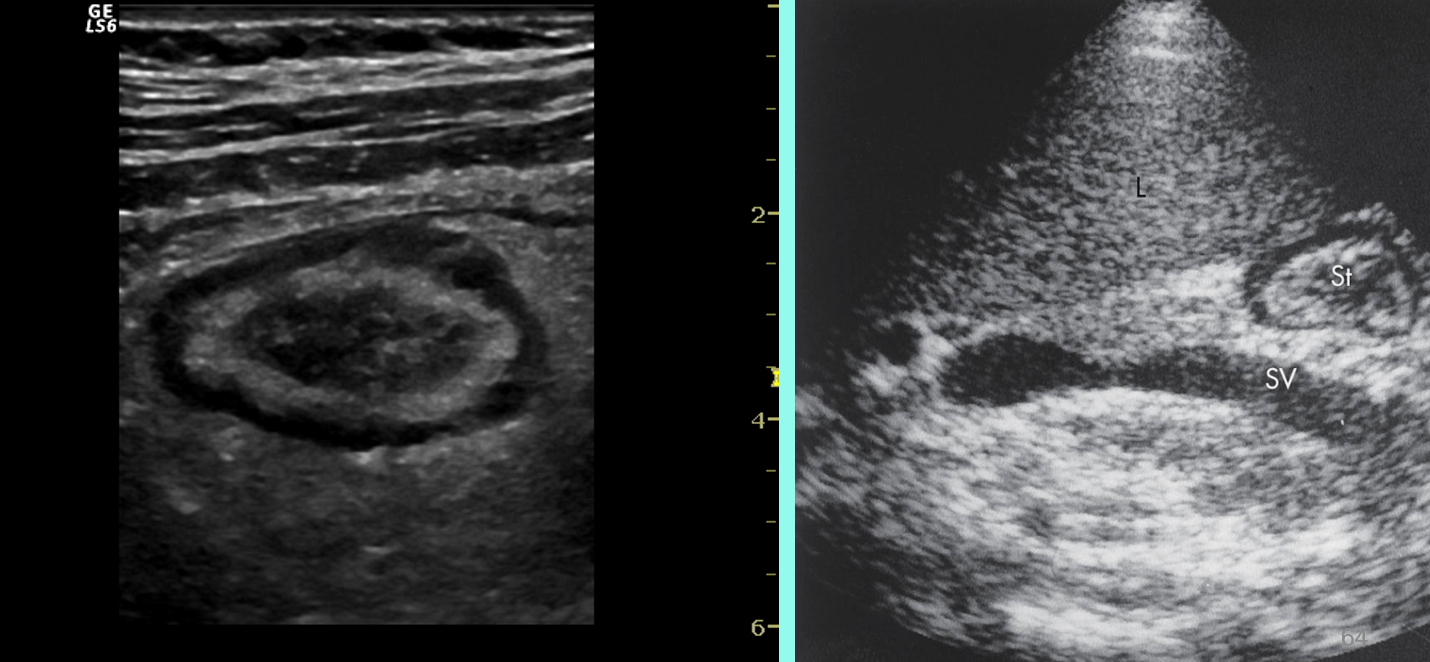

what is shown?

target or donut sign associated with intussusception

pseudokidney sign (intussusception- long axis)

sandwich sign (intussusception- long axis)